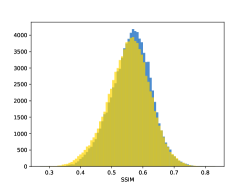

To visualise similarity metrics that compare image pairs (RMSE, SRE, SSIM) two metric distributions are generated: intra-similarity and inter-similarity. For each compared sample 300 random images are selected. The inter-similarity distribution is calculated for each image pair combination from both compared samples e.g. generated images of COVID-19 and real images of COVID-19. For the intra-similarity, all pairs of images in a single sample e.g real images of COVID-19 are considered. By comparing the shape of intra-similarity for the training subsample (Dataset) with the inter-similarity of training and generated samples the quality of the generated sample can be judged. It is also possible to compare in this way between the four image classes present in the dataset. The resulting distributions of inter-similarity of COVID-19 and the three remaining classes are compared in Fig. 4 to distributions of intra-similarity of the COVID-19 sample for each metric. All metrics, as expected based on available medical evidence Rubin et al. (2020), indicate that there are visible differences not only between COVID-19 and normal samples but also between viral pneumonia and lung opacity. Therefore, all classes should be distinguishable.

To visualise differences between synthetic and real samples distributions are generated for each of the RMSE, SRE and SSIM metrics: intra-similarity and inter-similarity. For each compared sample 300 random images are selected. The inter-similarity distribution is calculated for each image pair combination from both compared samples e.g. generated images of COVID-19 and real images of COVID-19. For the intra-similarity, all pairs of images in a single sample e.g real images of COVID-19 are considered. The distributions for generated samples describe very well the distributions for corresponding real images as shown in Fig. 6.

The quality of generated images is also confirmed with classical similarity metrics. The distributions of those similarity measures between generated and real images are compared for each sample with the distribution obtained within the real samples 6. The distributions for generated samples describe very well the distributions for corresponding real images. For an example see the results for the SSIM metric presented in Fig. 10. The small visible differences are almost insignificant compared to differences observed between the classes in Fig. 4.